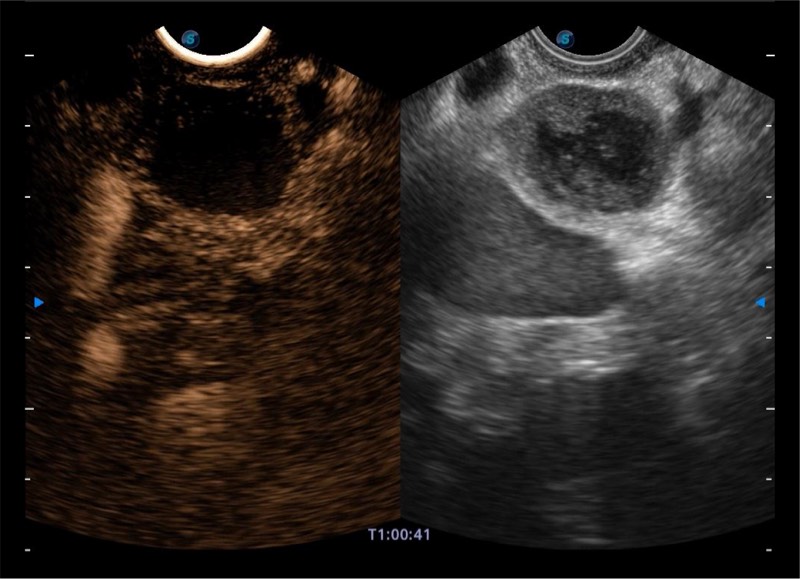

基于二十年的超声技术积累,MILE米乐集团官网提供了最新一代的独立超声主机,在提供高质量图像的同时满足多学科使用。具备常见多普勒技术并提供弹性成像、声学造影等高端影像技术。新一代传感器具有更强的抗干扰能力并减少图像伪影。